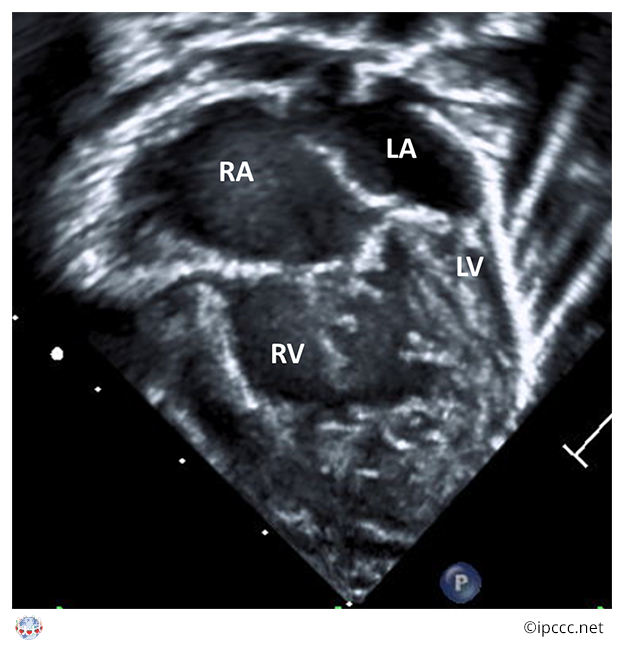

A spectrum of congenital cardiovascular malformations with normally aligned great arteries without a common atrioventricular junction, characterized by underdevelopment of the left heart with significant hypoplasia of the left ventricle including atresia, stenosis, or hypoplasia of the aortic or mitral valve, or both valves, and hypoplasia of the ascending aorta and aortic arch.

Echocardiogram